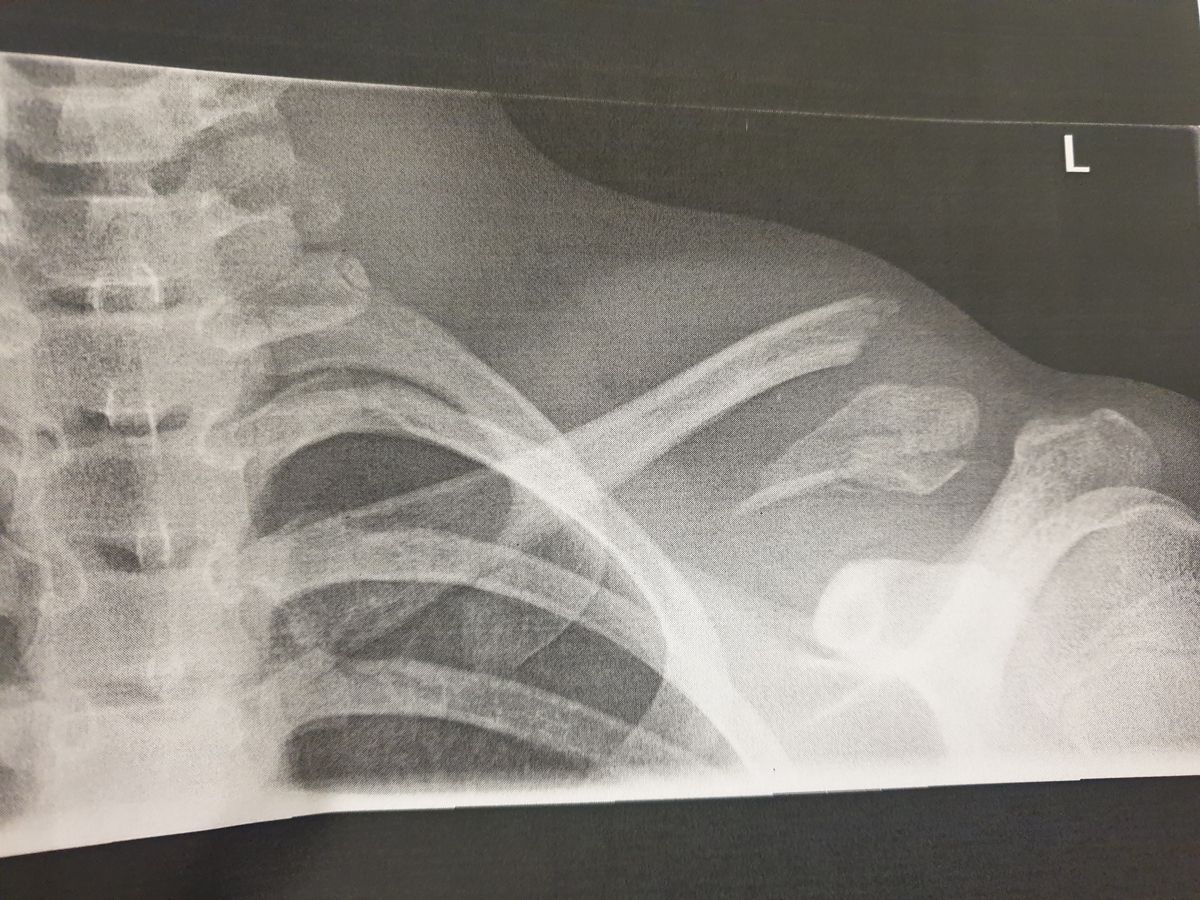

Taken to Brighton's Royal Alexandra Children's Hospital, an x-ray revealed that Tom had broken his collarbone on the left side and had a hematoma – a swelling where blood collects outside the blood vessels – because a small piece of bone had penetrated his muscle.